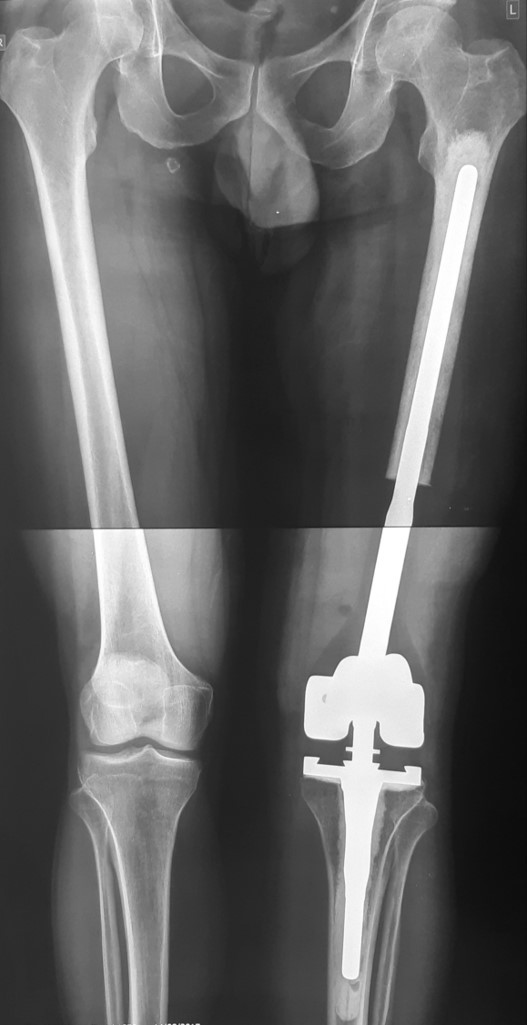

1 . ՌԴ-ում երկրորդային բնույթի կոտրվածքի ֆիքսացիա իրականացնելուց հետո՝ 40-ամյա բուժառուն դիմել է «Նաիրի» ԲԿ։ Բուժառուի մոտ ախտորոշվել է ոսկրային պլազմոցիտոմա։ Քիմոթերապիա ստանալուց հետո՝ 40-ամյա բուժառուն վիրահատվել է։ Կոնք-ազդրային հոդի հետ միասին հեռացվել է ազդրոսկրի վերին երրորդականը։ Առաջացած դեֆորմացիան շտկվել է էնդոպրոթեզով: «Նաիրի» ԲԿ-ի փորձառու թիմի և պրոֆեսիոնալ մոտեցման շնորհիվ՝ հաջողվել է պահպանել բուժառուի գործող վերջույթը։

Վիրահատությունից առաջ

Վիրահատությունից հետո